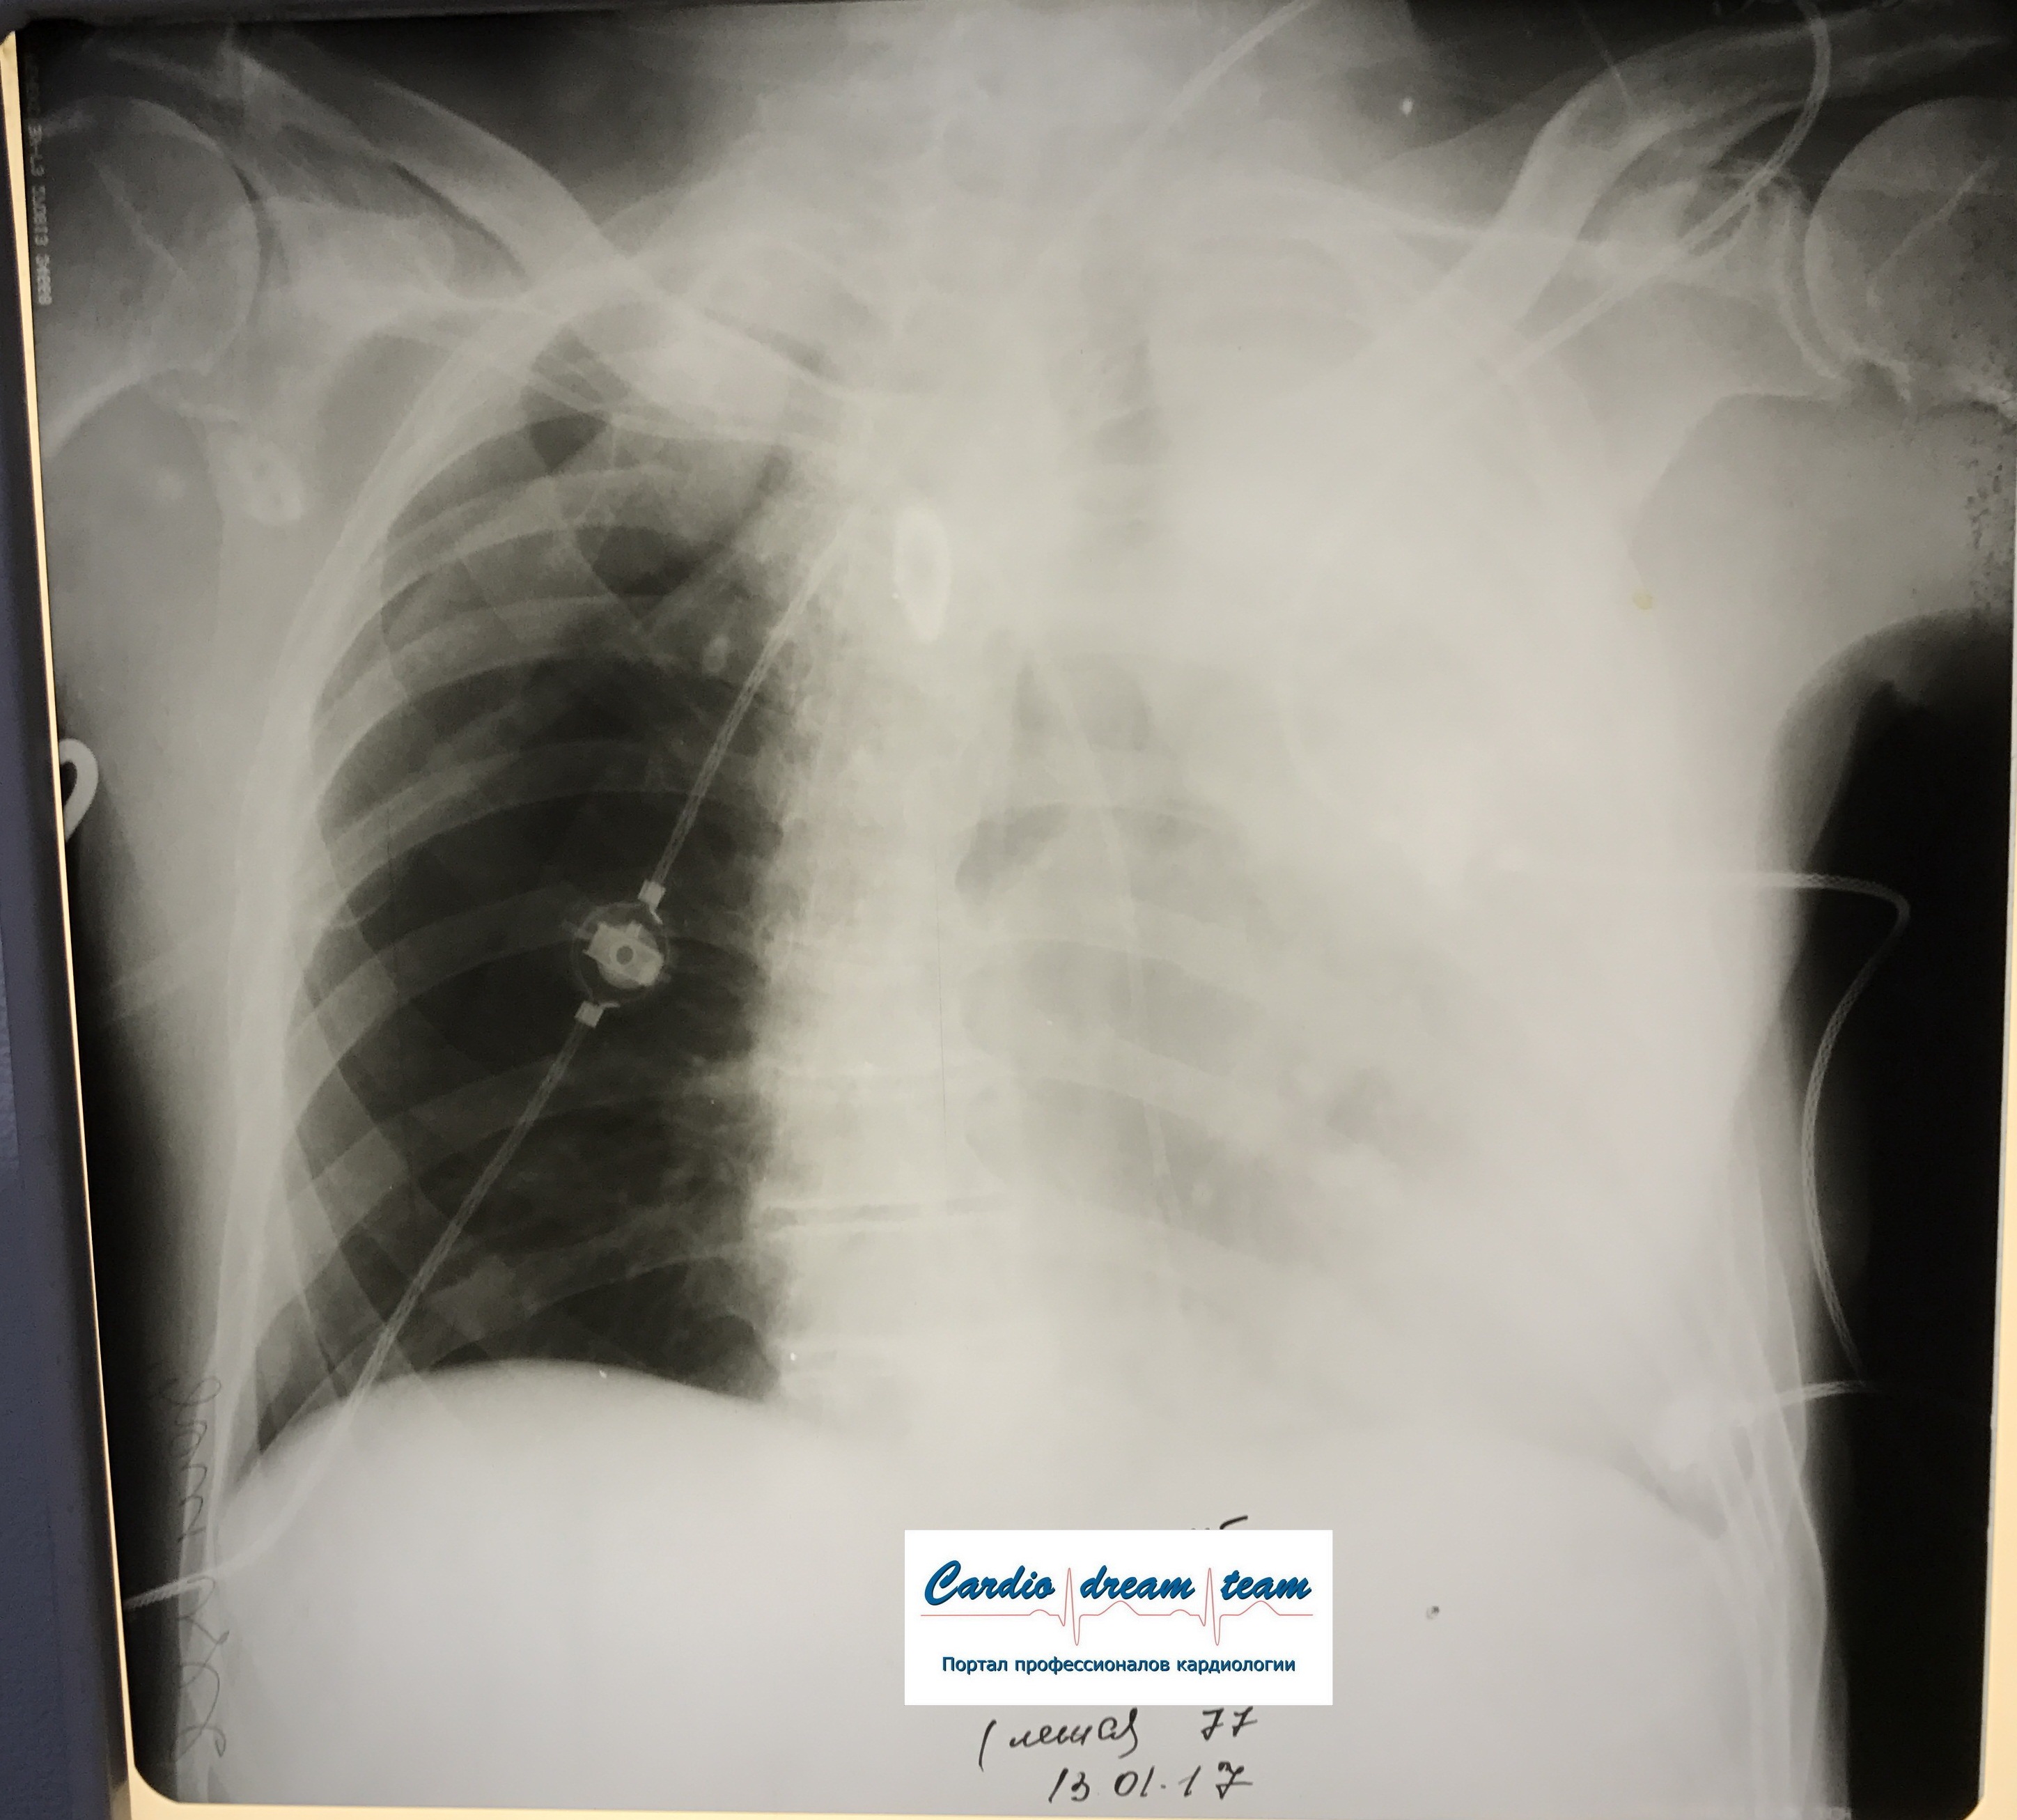

Ателектаз справа. Центральный рак.

Обсуждалось в Госпитале Ослабленных Сердец